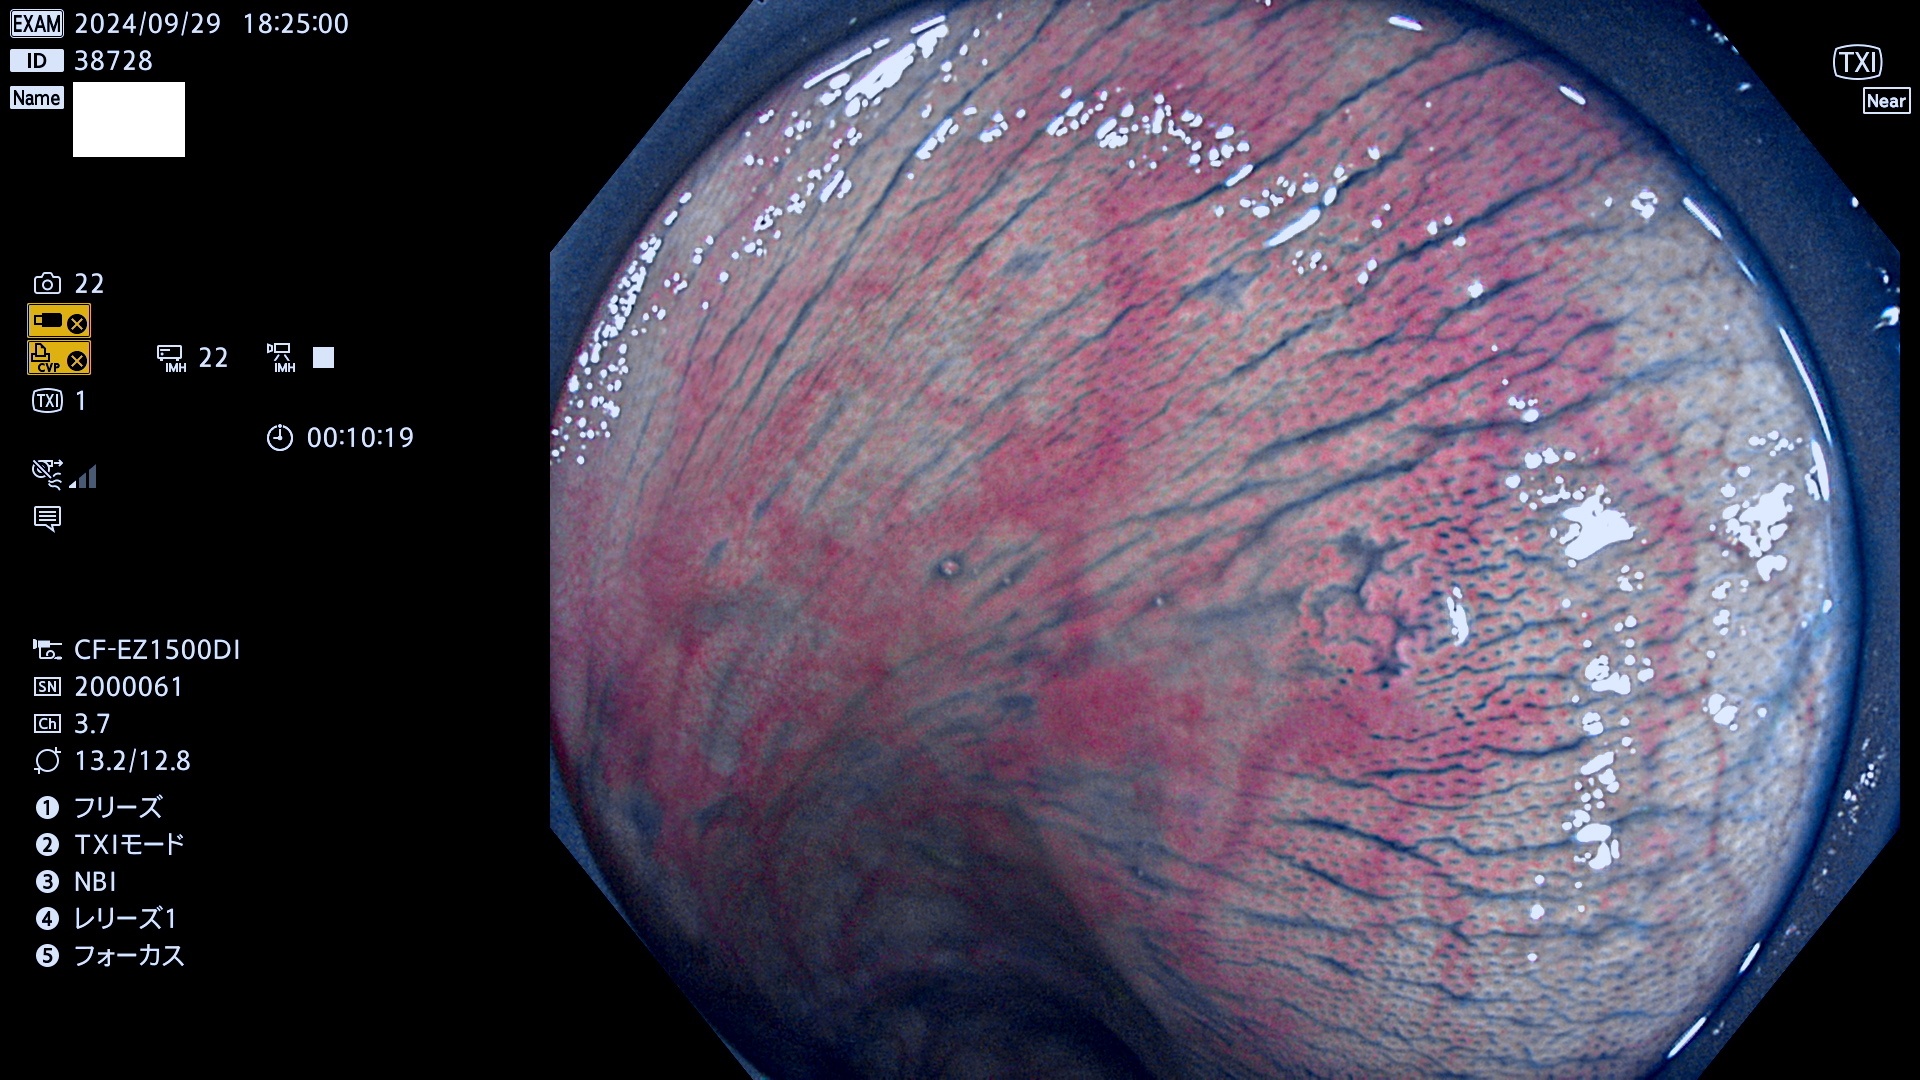

完全に平坦な物をUb、陥凹している物をUcと呼びます。最も発見が難しく危険な病変です。

毎週の検査(木・金・土・日)に発見されたUb、Uc型・腺腫を、その週の日曜の夜にUPし1週間、提示します。

抽出の対象期間 2024年9月26日〜9月29日の4日間(48件の検査)12件 (12/48=25%)